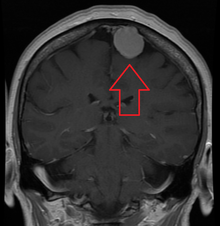

MRI image of a meningioma with contrast

Meningiomas are visualized readily with contrast CT, MRI with gadolinium,[14] and arteriography, all attributed to the fact that meningiomas are extra-axial and vascularized. CSF protein usually is elevated if lumbar puncture is attempted.